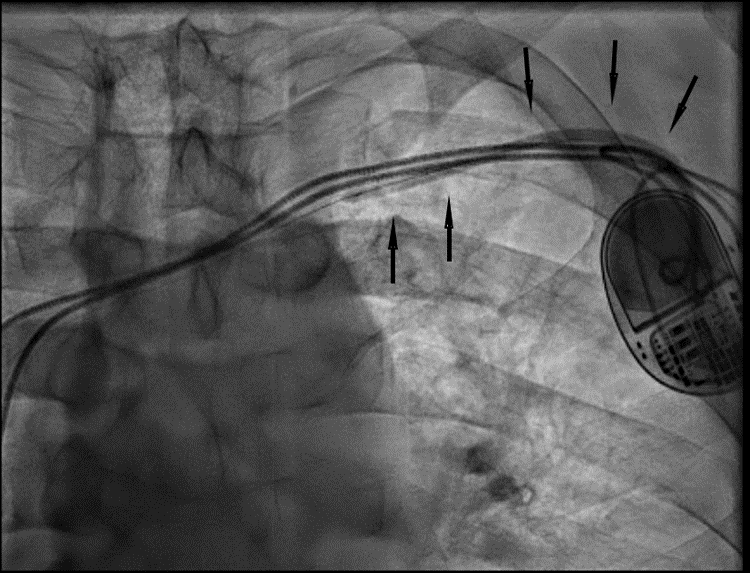

RHC procedure. Arm venous access was obtained with ultrasound guidance in all cases. After successful ‘radial’ sheath insertion, a 5-French (Fr) or 6-Fr balloon flotation right heart catheter was advanced (either by itself or over a 0.014-inch coronary guidewire based on operator preference) through the sheath and then into the pulmonary artery (PA). If resistance to catheter passage was encountered, a venogram (Figures 1A, 2A, and 3A) was performed using diluted contrast (50% saline) to determine the venous anatomy, the location, and the extent of stenosis, and to guide further wire/catheter advancement. In some cases, using different guidewires or catheters (eg, downsizing a 6 Fr to a 5 Fr) allowed RHC success. When a 0.014-inch wire was advanced into the superior vena cava (SVC) and the passage of a balloon-tip right heart catheter over the wire was unsuccessful due to a stenosis and/or pacemaker/ICD wires, a coronary balloon or 0.014-inch compatible peripheral balloon was then advanced over the wire and dilatation of the stenosis was performed (Figures 1B, 2B, and 3B). In some cases, a single balloon dilatation allowed passage of the RHC catheter. In others, a progressive increase in balloon diameters was needed. At the end of the procedure, the venous sheath was withdrawn, and manual compression was applied to the puncture site until hemostasis was attained.

We were able to pass a guidewire through all stenoses. A coronary or peripheral balloon catheter was then passed over the guidewire, and dilatation was performed (Figures 1B, 2B, and 3B). Coronary angioplasty balloons were utilized in 8 (44.4%), peripheral balloons in 7 (38.9%), and both peripheral and coronary balloons in 3 patients (16.7%). The balloons used were predominantly non-compliant (83.3%). Eleven patients (61.1%) required only a single balloon for successful venoplasty, while 7 patients (38.9%) had at least 2 balloons used, upsizing from the previously used balloon. The balloons' median diameter and length were 4 mm (range, 3-4 mm) and 60 mm (range, 20-200 mm), respectively. The median highest inflation pressure used was 14 atm (range, 8-18). After SVS dilatation, we performed successful RHC in 100% of the cases with a catheter passed into the PA. The average length of the procedure for successful RHC was 35.2 ± 15.5 minutes. There were no complications at the end of the procedure in any of our patients.